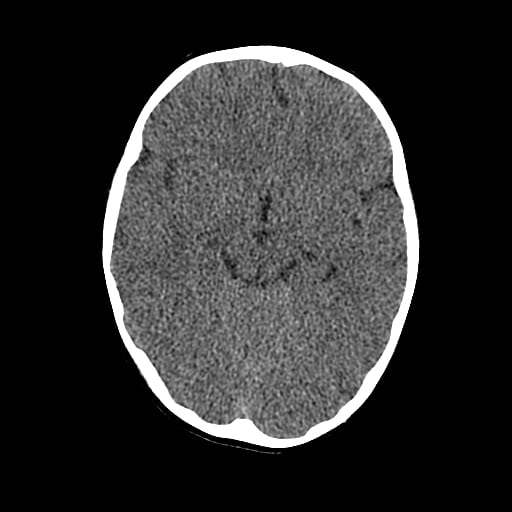

Age: 1

Sex: Male

Indication: Fall